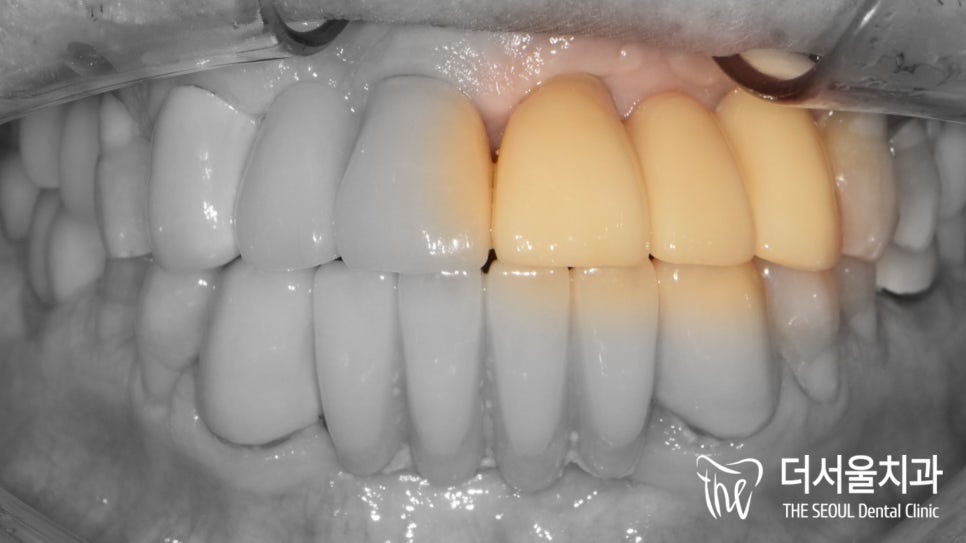

안녕하세요, 글쓴이 박현준 원장입니다. 오늘은 상악동 거상술 및 뼈이식과, 같이 임플란트 수술을 진행했던 증례입니다. 아래 사진으로 바로 설명드릴게요.